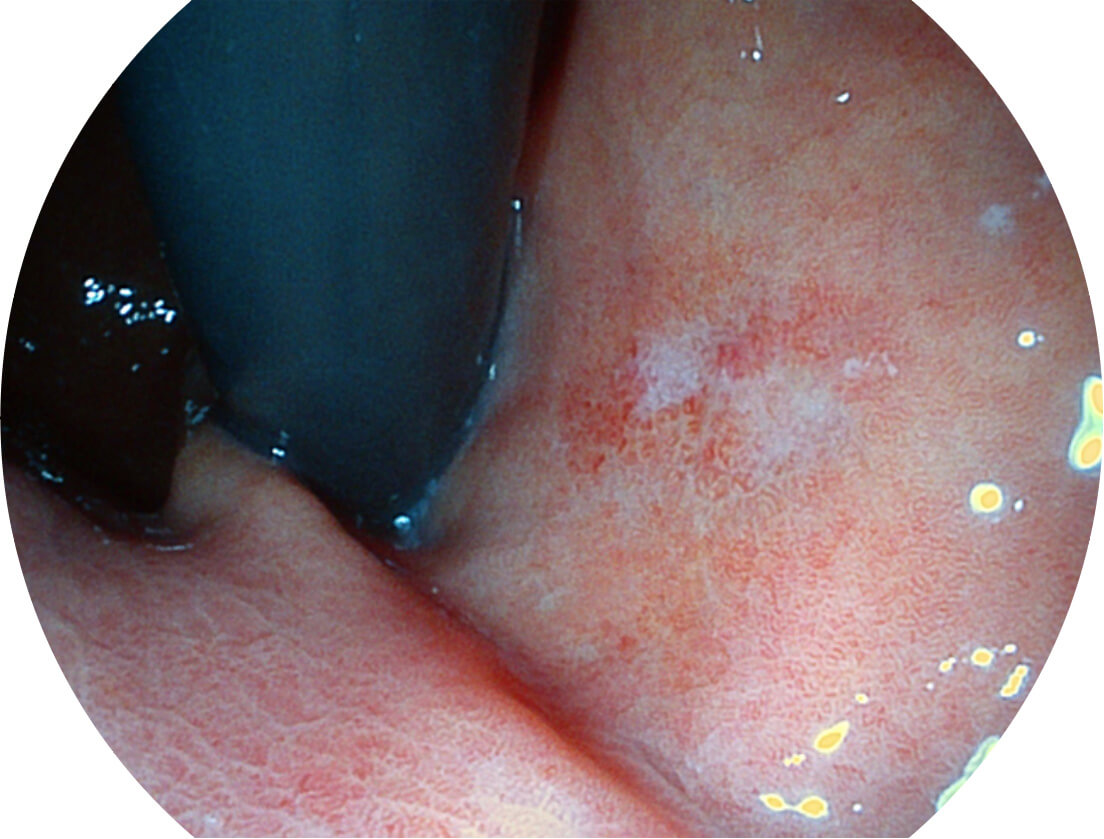

强调浅层黏膜结构的同时,保证照明亮度和提升浅层微血管与中层血管颜色对比度,病变边界更清晰。

采用光路合束技术,光谱自由度高,实现了更丰富的照明模式,染色模式SFI及VIST,从远景到近景,助力消化道早期疾病诊断。